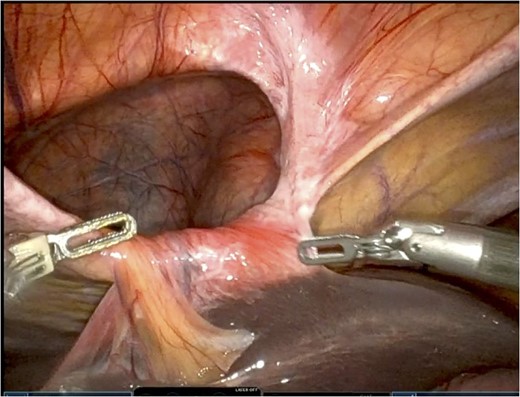

He was admitted for nasogastric decompression and underwent an upper endoscopy with benign findings. Once stable, he was discharged and optimized as an outpatient by adhering to a high-protein liquid diet. He underwent a scheduled robotic-assisted transabdominal preperitoneal (r-TAPP) repair of a type 4 anterior diaphragmatic hernia with mesh. The robot was docked and targeted with four 8 mm robotic ports across the mid-abdomen. A moderately sized hernia containing a loop of the transverse colon was identified. This was gently reduced (Fig. 3).

The falciform ligament was taken down with bipolar cautery. A peritoneal flap was created commencing about 4 cm inferior to the defect. A preperitoneal dissection was then performed to create the flap and to reduce the sac out of the mediastinum (Fig. 4).